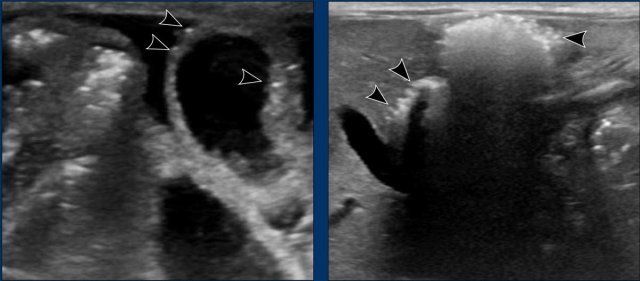

Images

Radiograph of a 2 month old baby with bilious vomiting after diaphragmatic hernia operation. There is very little bowel air consistent with the vomiting and collapsed bowel. On ultrasound ascites and a distended bowel loop with decreased perfusion are seen. In the mesentery a twist of the vessels is seen consistent with volvulus.

Volvulus

Video of a 2 month old baby with heavy vomiting.

There is a vascular twist with the superior mesenteric artery lying to the right of the superior mesenteric vein.